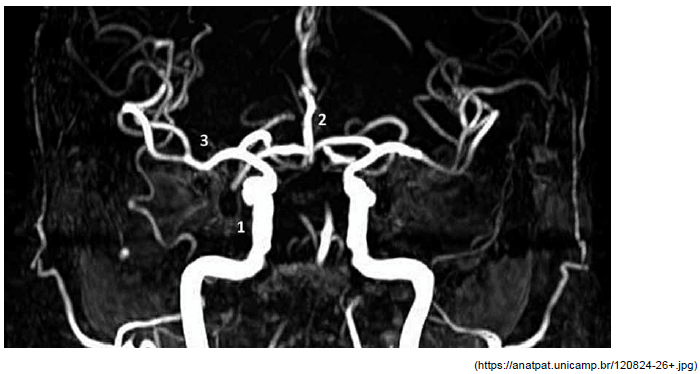

Assinale a alternativa que contempla, correta e respectivamente, as estruturas identificadas na imagem a seguir, na sequência 1, 2 e 3.

Provas